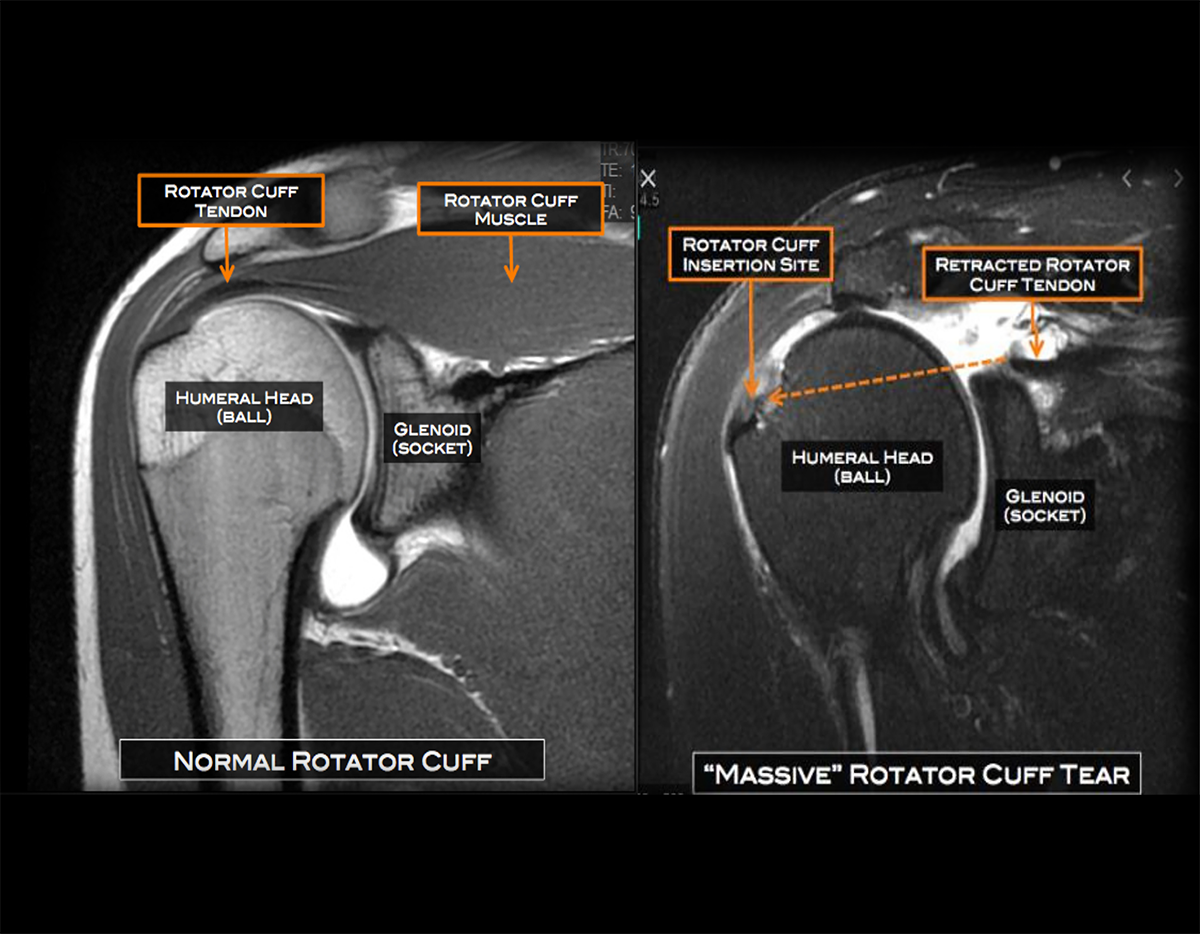

Imaging Tests: MRI, ultrasound, or X-ray can confirm the severity of the tear.